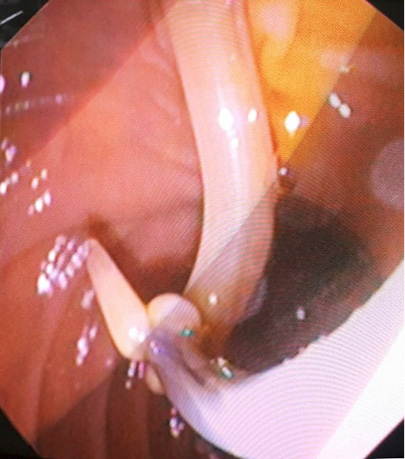

Pacientei įtarta pilvo skausmų priežastis – tulžies latakų akmenligė, nesant mechaninės geltos. Priimtas sprendimas atlikti duodenoskopiją ir ERC tyrimą. Duodenoskopijos metu įvertinta, kad papilla Vateri yra po PST procedūros. Kontrastavus BTL, pastebėtas >5 cm ilgio 4 mm skersmens prisipildymo defektas lygiais kontūrais. Naudojant Dormia krepšelį, iš tulžies latako pašalintas prisipildymo defektas – askaridė (3–5 pav.). Atlikus procedūrą, pacientės sveikatos būklė pagerėjo, pilvo skausmas regresavo, nesikartojo. Papildomai atlikta dehelmintizacija mebendazolu, antihelmintiniu vaistiniu preparatu („Vermox“).

3 pav. Askaridės šalinimas iš BTL, atliekant duodenoskopiją